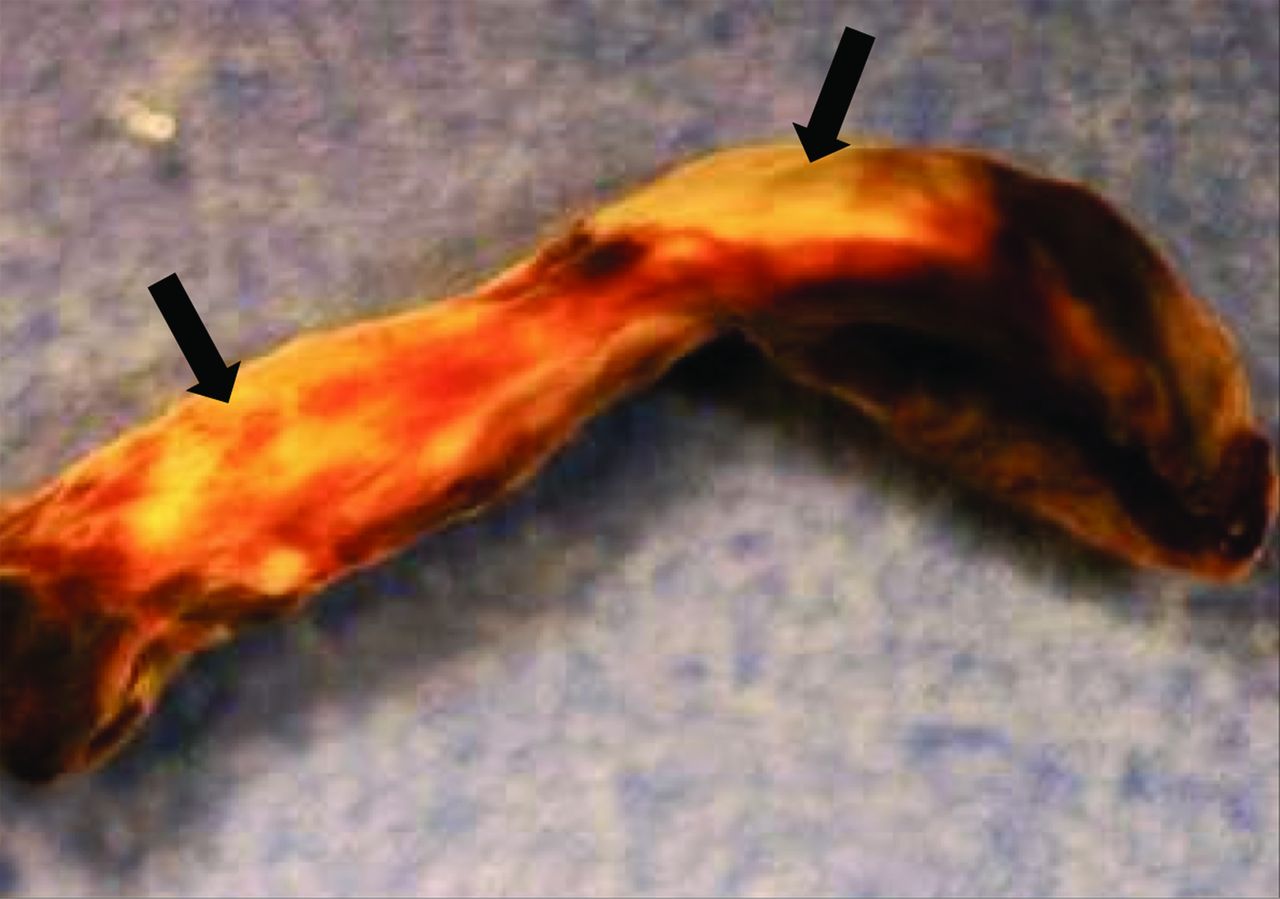

凝块被通过谢谢设备(n = 16), Accunet设备(n = 1),或直接与导游thrombo-aspiration导管阻塞网站(n = 1)。包括ICA(颈:n = 2;颅内:n = 7;两种:n = 1), MCA (n = 5)和基底动脉(n = 3)。宏观分析揭示了样本大小不同,形态和碎片。总值的光学显微镜标本显示特征暗示的一系列的流体动力学的力量可能是血栓。红色区域坐落在那里有可能低流或停滞或对血管壁的血栓,而白色区域有可能暴露在高剪切流(图1)。血栓性的组织元素,如纤维蛋白、血小板,红细胞,也不同在每个血栓和在各种血栓;因此,这些结果与早期的发现一致的组织学检查光学显微镜的凝块。12

这种血栓段特性相对光滑的表面形态。有强烈的白色和红色部分,表明暴露某些地区持续的高剪切流和其他地区停滞,分别。箭头表示位置的扫描电镜图片所示。

两个不同的结构模式与SEM可以认出:1)血栓展示先进成熟,所有的血栓性元素是如此密集集成单个实体没有清晰可辨的(图2),表明心脏稳定位置,持续暴露在剪切流;和2)血栓显示不同的纤维蛋白,红细胞被困,表明相对宽松的交联,一个活跃的地区特点的血栓仍在成熟的过程中,可能停滞的地区形成和再循环(图3)。这些模式被认为在不同比例在不同的患者。在某些情况下,可以联系具体的超微结构的研究结果推测病因的中风。值得注意的是这样一个广泛的血栓被恢复。